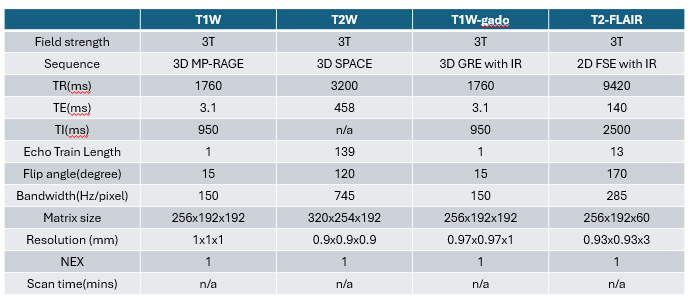

数据样本可视化

T1W 3D 图像